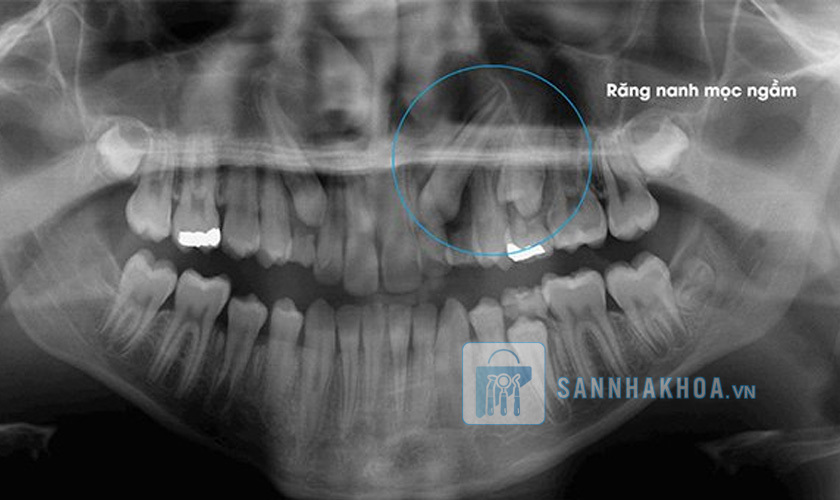

Răng nanh mọc ngầm là gì?

Răng nanh mọc ngầm là tình trạng răng nanh không mọc đúng vị trí trên cung hàm mà bị kẹt lại trong xương hàm hoặc nướu. Đây là hiện tượng thường gặp trong nha khoa, xảy ra do sự cản trở trong quá trình mọc răng hoặc do thiếu không gian trên cung hàm. Răng nanh thường bắt đầu mọc vào giai đoạn cuối của quá trình phát triển răng vĩnh viễn, khoảng từ 11 đến 13 tuổi. Khi gặp vấn đề về mọc ngầm, răng nanh không thể trồi lên bề mặt hoặc chỉ trồi lên một phần, gây ảnh hưởng đến cấu trúc hàm và chức năng răng miệng.

Chụp X-quang và hình ảnh 3D: Đây là công cụ không thể thiếu để bác sĩ xác định rõ vị trí răng mọc ngầm bên trong xương hàm. X-quang giúp bác sĩ nắm được hướng mọc, mức độ chèn ép vào răng lân cận hoặc các tổn thương xương hàm mà răng nanh mọc ngầm có thể gây ra.